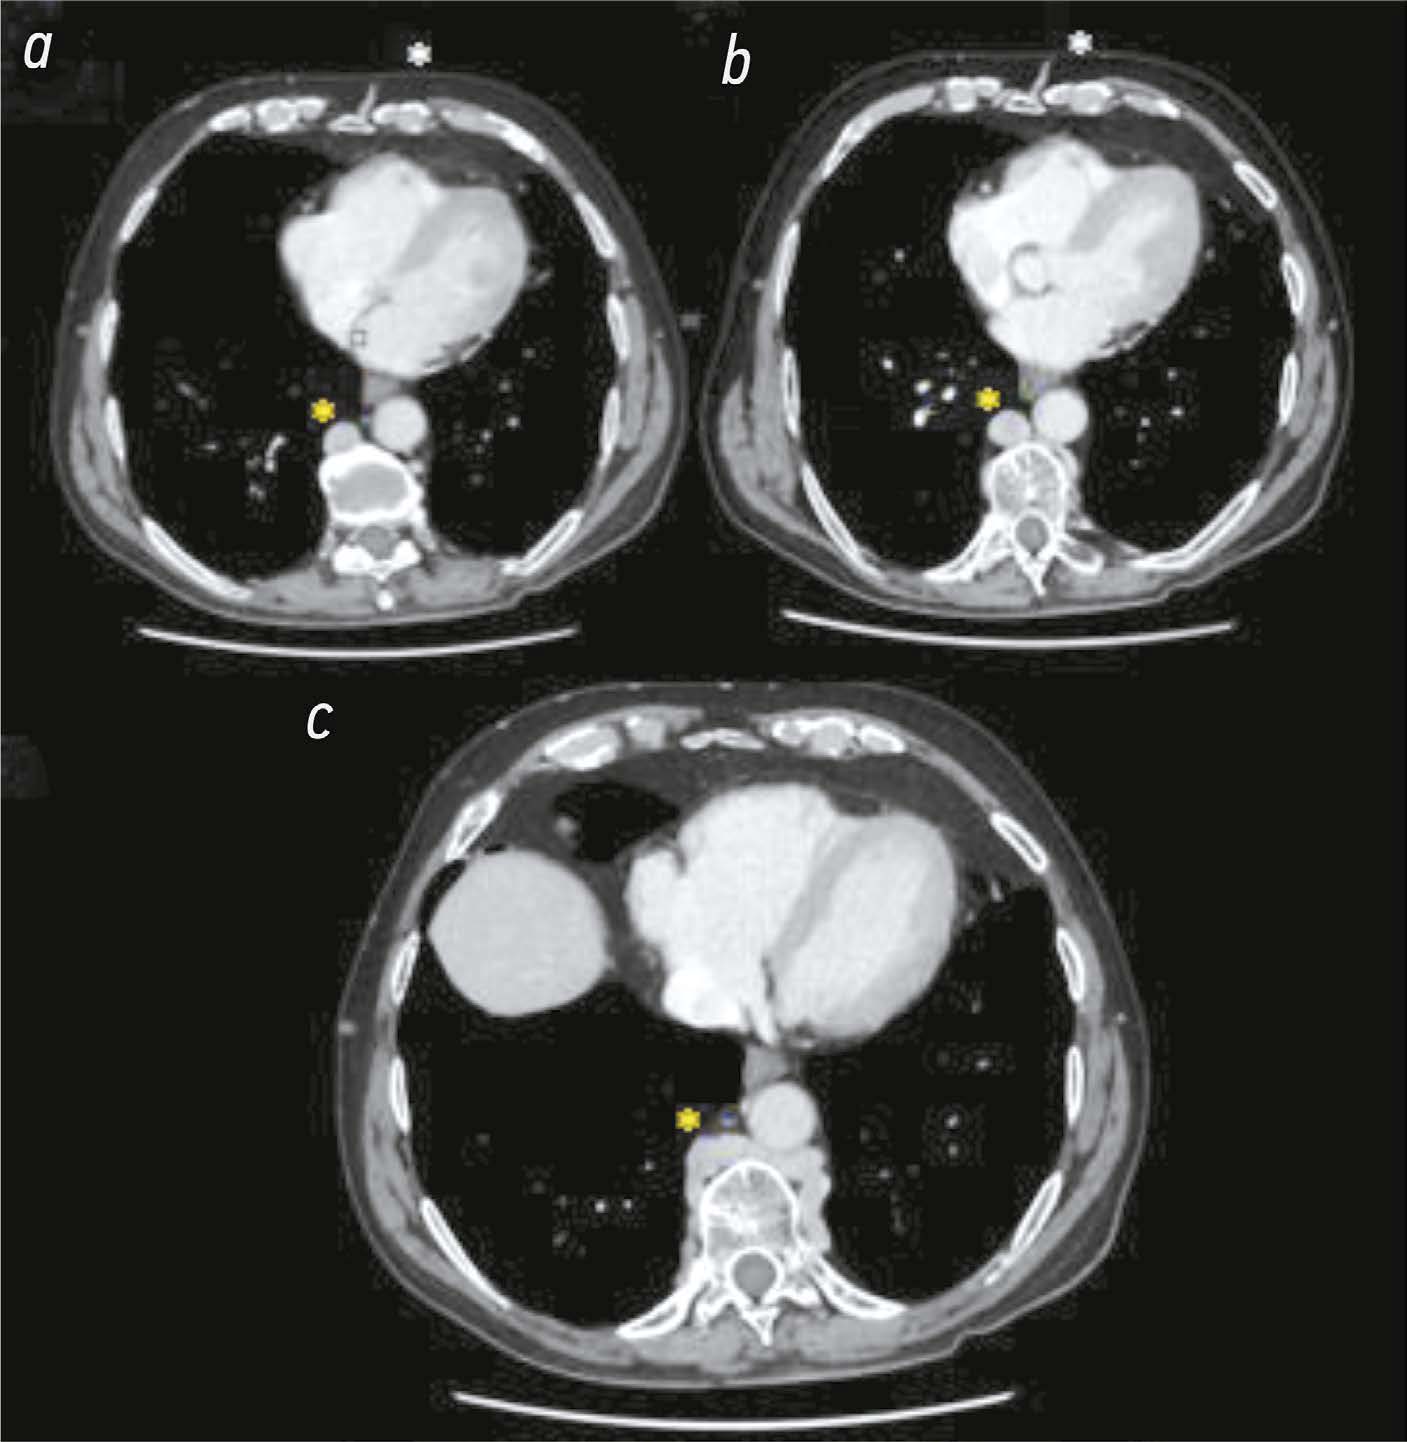

The role of computed tomography in the differential diagnosis of an intracardiac mass of the mitral valve: a case series

Abstract

The differential diagnosis of an echocardiographically detected intracardiac mass in the mitral annulus can be challenging and usually requires a multimodal approach. This type of lesion is very often associated with subvalvular calcification of the mitral valve. The rare, caseous, variant is the most difficult to diagnose. This case series highlights the clinical significance of computed tomography in detecting and characterizing subvalvular mitral annular calcification when other modalities, particularly echocardiography, are inconclusive. The aim of this article was to raise awareness among specialists of the classic signs of caseous subvalvular calcification of the mitral annulus when visualized with different modalities. Special attention is also given to providing a differential diagnostic series that identifies features that differentiate subvalvular calcification of the mitral annulus from other conditions at this site. Healthcare professionals need to be aware of these mitral valve lesions in order to predict possible associated complications and plan a treatment strategy that may help avoid unnecessary surgical procedures in some cases.

893-901